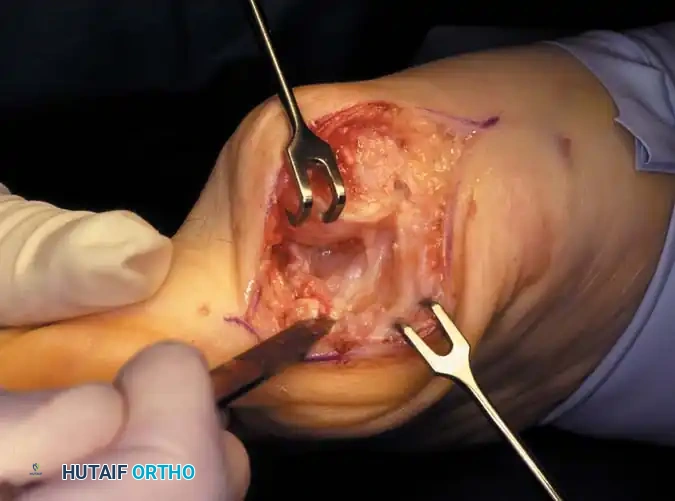

Modifi ed McBride Bunionectomy TECHNIQUE 78-1

SKIN AND CAPSULAR INCISION

• With the patient supine and a tourniquet on the limb, extend a midline, straight, medial incision from the middle of the proximal phalanx to 2 cm proximal to the junction of the medial eminence with the metatarsal shaft (Fig. 78-13). This incision usually is in an internervous plane between the most medial branches of the superfi cial peroneal nerve dorsally and the medial proper digital branch of the medial plantar nerve plantarward. (McBride recommended a single incision beginning at the fi rst web space and extending proximally and medially across the metatarsal, ending on the medial side of the fi rst metatarsal proximal to the exostosis.)

• Mobilize the skin 2 to 3 mm dorsally and plantarward to ensure that no sensory nerve would be injured by the capsular incision.

• Coagulate the superfi cial veins as encountered to minimize postoperative bleeding.

• Use delicate, two-tooth retractors and 1.5-mm forceps in this initial dissection to avoid unnecessary skin trauma.

• Make a longitudinal capsular incision (the original McBride capsular incision was transverse) 3 to 4 mm plantar to the line of the skin incision (Fig. 78-14).

Fig. 78-12 Hallux valgus treated by modifi ed McBride procedure. A, Preoperative deformity in 30-year-old patient. B, Correction obtained at surgery. C, Preoperative and postoperative radiographs (note fi bular sesamoid was not removed). More deformity can be corrected by fi bular sesamoidectomy, but overcorrection (hallux varus) is risk. If fi bular sesamoid is excised, medial capsule should be closed while holding hallux in 5 to 10 degrees valgus and kept in that position until capsular healing.

Fig. 78-13 Modifi ed McBride procedure: fi rst incision. Dotted line denotes dorsally curved incision; solid line indicates preferred incision (internervous plane).

Fig. 78-14 Modifi ed McBride procedure. Longitudinal capsular incision is 3 to 4 mm plantar to skin incision.

• By sharp dissection, raise the periosteum and the capsule dorsally and plantarward from the base of the proximal phalanx to the proximal edge of the medial eminence (Fig. 78-15). At the proximal end of the medial eminence, avoid releasing the proximal bony attachments of the medial capsule on the metatarsal neck (especially in the dorsal direction) in an attempt to expose the medial eminence. To ensure adequate exposure without disruption of this proximal attachment, a longitudinal capsular incision is suggested.

• Elevate the capsule by sharp dissection dorsalward and plantarward to expose the dorsal aspect of the metatarsal head, the entire medial eminence, and the plantar plate. A periosteal elevator is not recommended because of the possibility that the proximal attachments of the capsule may be released.

L-SHAPED CAPSULAR INCISION

• Alternatively, make the capsular incision in an inverted L shape (Fig. 78-16A).

• Raise the dorsal fl ap deep to the nerve and veins until the accessory slip of the extensor hallucis longus tendon is seen in the proximal portion of the incision where it is easier to identify. The tendon almost always can be located with careful searching. If it is not seen at the dorsomedial aspect of the fi rst metatarsal, however, begin the longitudinal limb of the incision at this slope of the metatarsal from dorsal to medial.

• Begin the incision proximally on the dorsomedial side of the fi rst metatarsal shaft and 2 to 3 mm medial to the accessory slip of the extensor hallucis longus tendon. Carry the incision to the bone at the level of the fi rst metatarsal joint, extending proximally 4 to 6 cm.

• Make the transverse limb of the capsular incision at the level of the joint, stopping 2 to 3 mm from the tibial sesamoid bone; this limb transects the capsular insertion of the abductor hallucis muscle (Fig. 78-16B and C).

Fig. 78-15 Modifi ed McBride procedure. Capsule is opened, and attachment of capsule on metatarsal neck (arrow) is carefully preserved.

• Beginning on the plantar aspect of the incision, remove the capsule from the medial eminence from the inside out. Avoid buttonholing the capsule at the junction of the medial eminence and the metatarsal by directing the small-bladed knife down the slope of the eminence.

• Free the capsule subperiosteally on its dorsomedial surface, and retract it proximally and plantarward (Fig. 78-16D).

• Insert one small Hohmann retractor over the dorsolateral surface of the metatarsal head and another beneath the head at the head and neck junction, while distracting and plantar fl exing the hallux to expose the articular surface of the metatarsal head for evaluation of its condition and orientation. Reduce the hallux congruently on the metatarsal head.

• If the hallux is in more than 15 degrees of valgus after reduction, a distal metatarsal osteotomy is needed.

MEDIAL EMINENCE REMOVAL

• After inspecting the metatarsophalangeal joint for degenerative changes, loose bodies, or synovial abnormalities, remove the medial eminence by fi rst scoring with an osteotome its proximal edge where the eminence meets the shaft. Always consult the preoperative radiographs to determine how much of the medial eminence should be removed.

• Using the same osteotome or a power saw, begin the exostectomy distally at the parasagittal groove, and direct it medially toward the scored area on the metatarsal shaft (Fig. 7817). If a power saw is used, a 9-mm blade, rather than a 4to 5mm blade, is preferred. The medial direction of the osteotomy prevents splitting of the metatarsal shaft, especially if the proximal edge of the osteotomy has been scored as recommended.

• After the medial eminence has been removed, use a small rongeur to round off the dorsal and plantar edges of the medial aspect of the metatarsal head. Rasping the raw bone concludes the initial stage of the procedure. Use bone wax on the raw surfaces of bone of the metatarsal head.

ADDUCTOR TENDON AND LATERAL CAPSULAR RELEASE

• Begin the second stage with a dorsal longitudinal incision beginning 2 to 3 mm proximal to the dorsal aspect of the fi rst web space to avoid web contracture postoperatively; extend it proximally between the fi rst and second metatarsal heads for 3 to 4 cm (Fig. 78-18). This allows adequate exposure of the adductor insertion into the base of the proximal phalanx, the lateral head of the fl exor hallucis brevis muscle converging on the fi bular sesamoid, and the entire lateral capsule from the extensor hallucis longus muscle to the plantar plate.